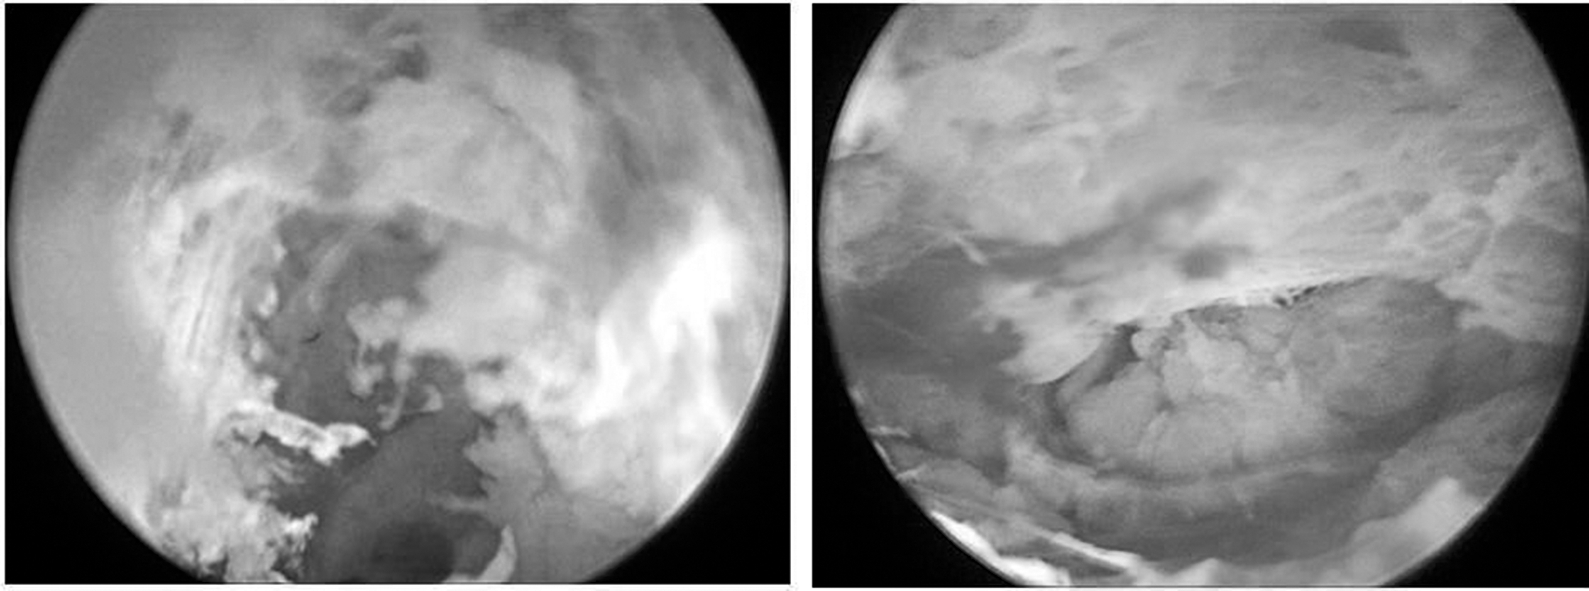

Полученные данные позволили применить разработанный малоинвазивный метод для лечения данного больного. Малотравматичными разрезами, до 2,0 см, по медиальному и латеральному краям стопы в проекции гнойного очага выполнено вскрытие флегмоны, получено 15 мл желтоватого гнойного отделяемого без запаха, взят посев. В раны установлен артроскоп в тубусе с одномоментной подачей раствора антисептика, выполнена эндовидеоскопическая санация и ревизия ран. Визуализировано глубокое подошвенное клетчаточное пространство, выявлено большое количество детрита и мягкие ткани, покрытые фибрином. В выявленных очагах выполнена хирургическая обработка ультразвуковой кавитацией с последующей эндовидеоскопической ревизией (рис. 2).

Рис. 2. Эндовидеоскопическая визуализация ран до и после хирургической обработки